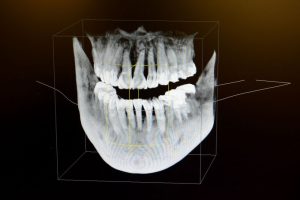

3D Imaging is effective for diagnosing conditions as well as planning treatments. Some of the benefits of 3D Imaging can include but are not limited to:

- Effective planning for dental implant placement

- Evaluating the jaws and face

- Viewing the head and neck as a whole

- Visualizing abnormal teeth

One of the advantages of 3D Imaging technology is that it provides our staff with a view of your mouth and the supporting structures which can be more comprehensive than digital x-rays.